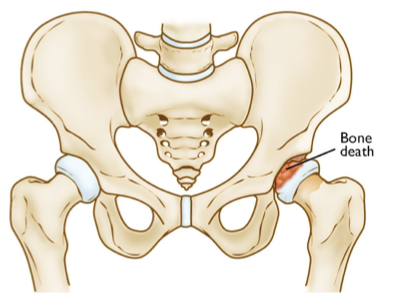

legg-calve perthes

_______________ is avascular necrosis of the hip in childhood

epiphyseal plate

legg-calve perthes is decreased blood to the ______________

3-12

5-7

legg-calve perthes occurs from ages _____-_____ but is most common from ages ______-_____

males

legg-calve perthes occurs more in (females or males)

T

T/F: maternal smoking and secondhad smoke can play a factor in a child developing legg-calve perthes

it’s the same but legg-calve perthes is non-weight bearing

what’s the difference in hip dysplasia and legg-calve perthes casting

less than 6

if the a child has legg-calve perthes and they are age ________, conservative treatment is recommended